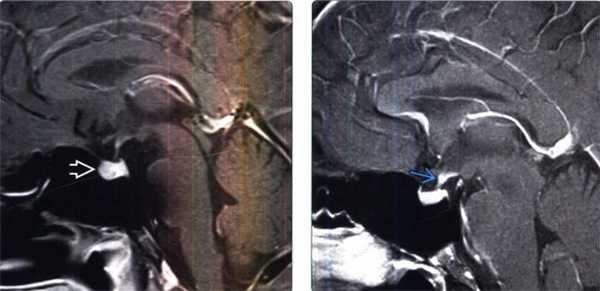

2. МРТ признаки лимфоцитарного гипофизита:

• Т1-ВИ:

о Утолщение ножки гипофиза (> 2 мм + исчезновение его нормального сужения) о ± увеличение размеров гипофиза

о В 75% случаев наблюдается отсутствие «яркого пятна» задней доли гипофиза

• Т2-ВИ:

о Изо-/гипоинтенсивный сигнал

• Постконтрастные Т1-ВИ:

о Интенсивное и равномерное контрастное усиление

о Может наблюдаться утолщение твердой мозговой оболочки или слизистой оболочки основной пазухи носа